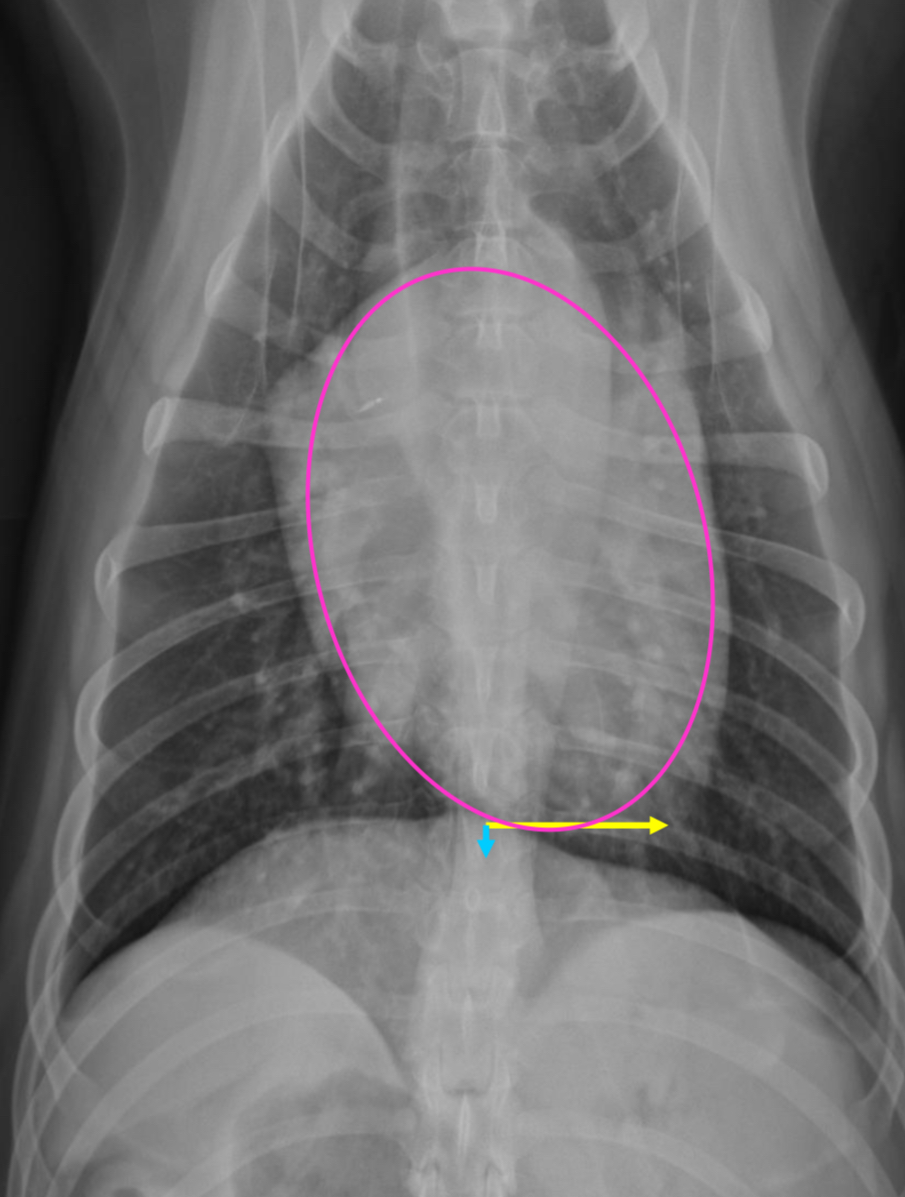

RAE feature on VD

Bulge at 9-11 o’clock region ± RVE bulge

What part of the heart is enlarged?

RAE

2 features of RVE on VD

-bulge 5-9 o’clock

-reverse D

What part of the heart is enlarged

RVE